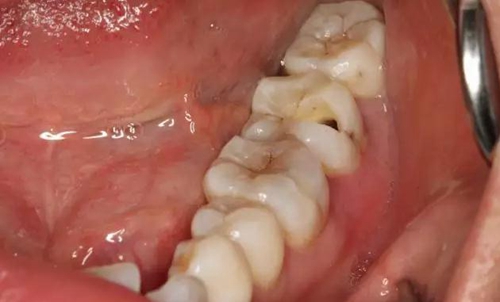

圖2.  37牙冠基本完好,松動(dòng)Ⅰ度。合面有一開髓孔被棉球覆蓋,頰側(cè)牙齦輕度紅腫。

2.jpg